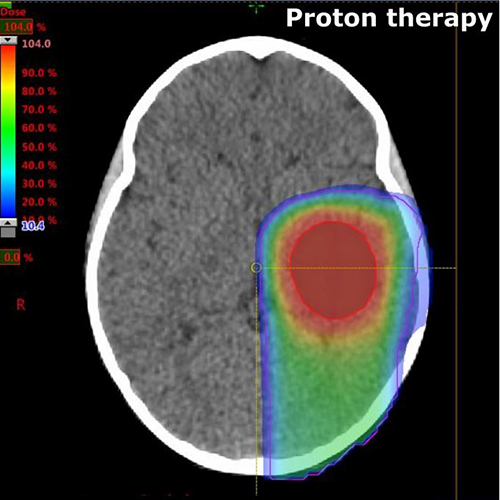

Compared to conventional x-ray (photon) therapy, proton beam therapy superiorly targets tumours and cancer cells, delivering optimal radiation doses to the tumour while limiting the effects on the surrounding healthy tissues.

Protons are designed to deposit radiation more conformally to the target volume, sparing both the healthy tissues before and beyond the target as well as critical structures surrounding the tumour.

Radiotherapy is responsible for a range of mild to severe neurologic, endocrine and cognitive negative effects in children. Because proton therapy is more targeted, it is the preferred treatment for children.